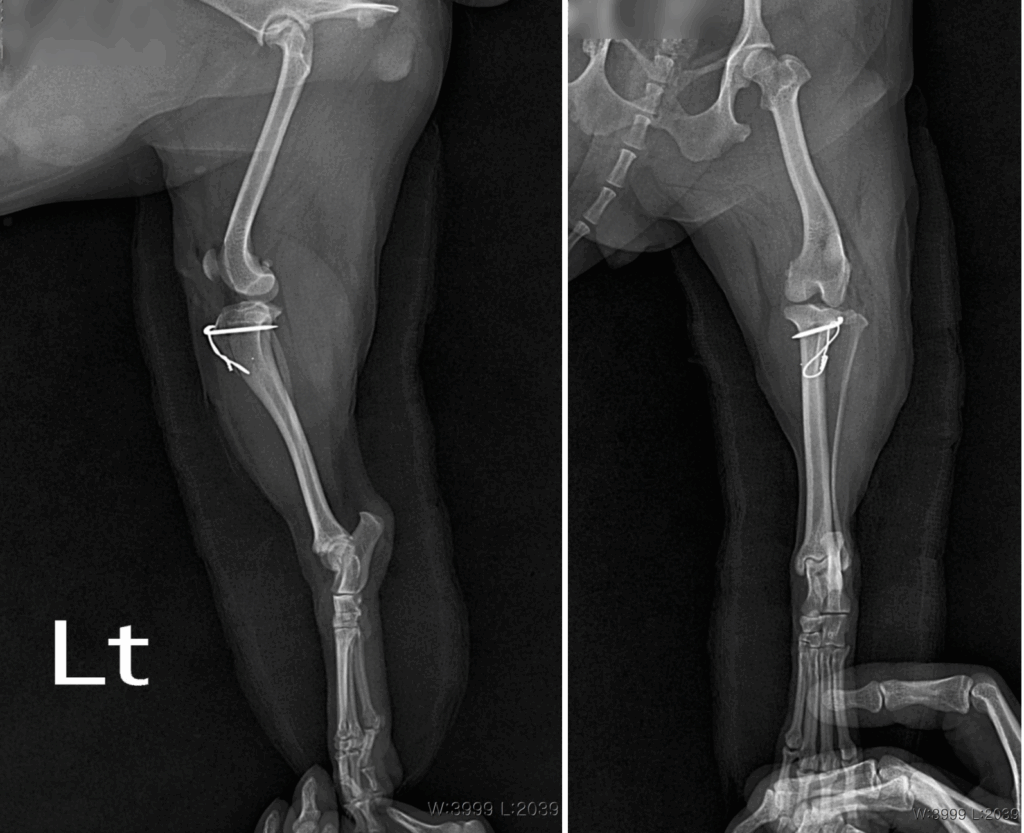

수술 후 방사선 검사 / 출처: 24시온숲동물의료센터

신체검사와 촉진, 방사선 검사를 통해 구름이의 무릎 상태를 확인했습니다.

그 결과, 좌측 슬개골 탈구 2~3기, 3기에 가까운 상태로 진단되었습니다.

환자는 수술적 교정이 필요하다고 판단하였고, 다음과 같은 수술 방법을 적용했습니다.

- Block Recession

대퇴골 활차구(슬개골이 움직이는 홈)를 깊게 만들어, 슬개골이 안정적으로 자리할 수 있도록 교정 - Lateral Imbrication

무릎 관절 외측의 연부조직을 강화하여, 탈구 방향으로 당겨지는 힘을 줄이고 안정성 확보 - TTT (Tibial Tuberosity Transposition)

정강이뼈 부착 부위를 옮겨 슬개골이 정중앙에서 움직이도록 축을 교정